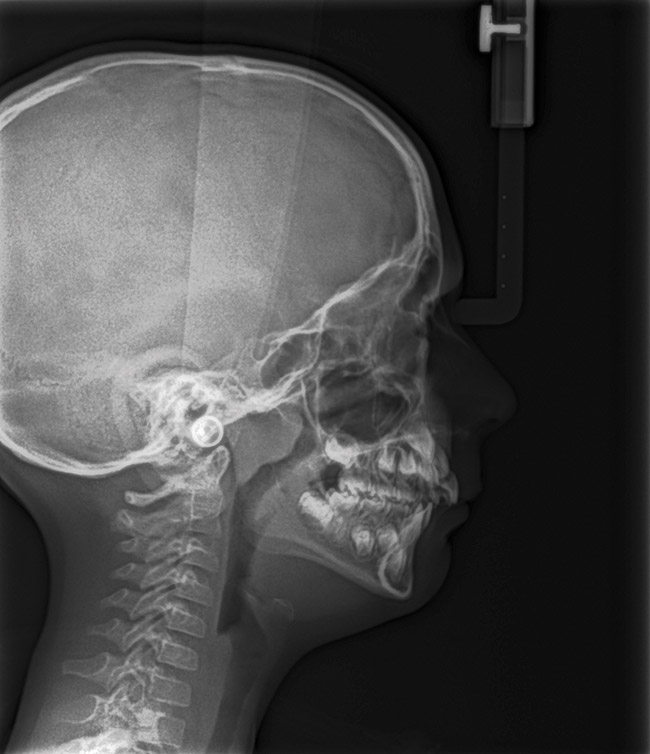

(13.) Seven-year-old brachyfacial child with high body mass index (Case courtesy of James Awbrey, DMD).

Figure 13

(14.) Angle Class III occlusion with constricted maxilla.

Figure 14

(15.) Cephalometric evaluation demonstrates significant tonsillar blockage of the airway and bimaxillary retursion.

Figure 15